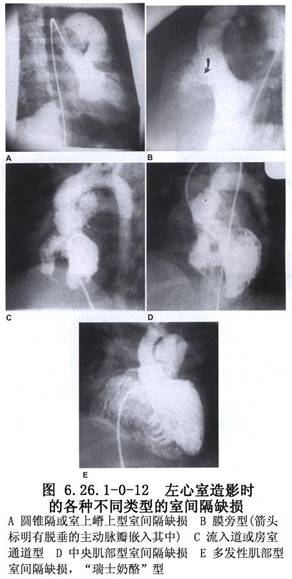

室間隔缺損的大小變異很大,按其口徑臨牀上大致可分爲大、中、小三型。大型室間隔缺損的口徑可以相當於或稍小於主動脈開口,因此右室壓力可接近於體循環壓力。中型室間隔缺損,又稱“限制性”室間隔缺損,其口徑約爲主動脈口徑的1/3~2/3,這類缺損可造成右室收縮壓升高,有的可高達左室收縮壓的50%,兩心室間有壓力階差存在;肺循環和體循環血流量比值上升到2~3.5倍。小型室間隔缺損,是指口徑小於主動脈口徑的1/3,右室收縮壓一般無明顯升高,肺循環和體循環血流量比值<1.75(圖6.26.1-0-8~6.26.1-0-12)。